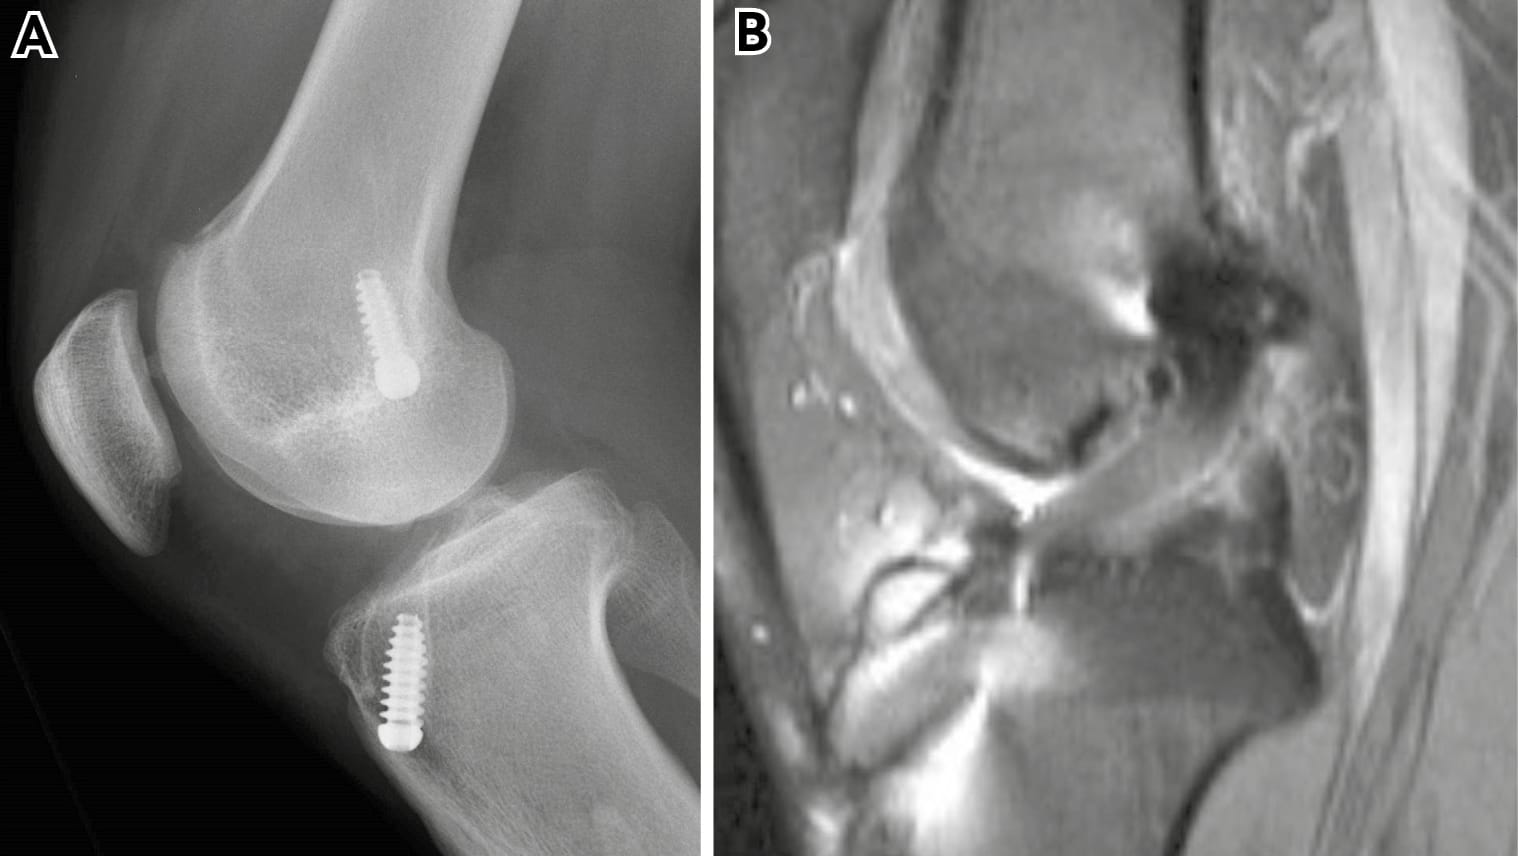

A full series of plain radiographs are important. These should include long leg alignment films and good lateral x-rays to assess the tibial slope (figure 1). There is a tendency for the eye to go straight to any metal implants but actually what is important is the position of the tunnel relative to these. The tunnel may be anterior, posterior, medial or lateral (or a combination) to the metal implant. It is for this reason it is rarely wise to comment on a previous surgeon’s tunnel position based on plain x-rays alone. The impression of a poorly placed tunnel may be completely incorrect (figure 2). This is particularly the case with grafts with bone blocks as the screw is normally adjacent to the bone block and therefore the soft tissue element of the graft may be some way away from the screws. Casual comments by a surgeon can lead to unfair lawsuits that could have been avoided.

CT scanning is much more valuable and as well as sagittal and coronal reformatting, a three-dimensional imaging can be provided. A CT based classification for femoral tunnel location has been described by Magnussen et al [3] Magnussen RA, Debieux P, Benjamin B, Lustig S, Demey, Servien E, Neyret P. A CT-based classification of prior ACL femoral tunnel location for planning revision ACL surgery. Knee Surg. Sports Traumatol. Arthroscopy. 2012; 20: 1298-1306. The three-dimensional reformatting capacity can be especially useful.